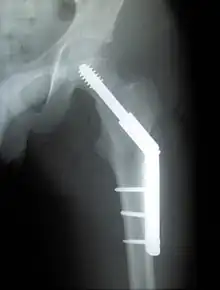

Fracture supported by dynamic hip screw

A trochanteric fracture, below the neck of the femur, has a good chance of healing.

Closed reduction may not be satisfactory and open reduction then becomes necessary.[42] The use of open reduction has been reported as 8-13% among pertrochanteric fractures, and 52% among intertrochanteric fractures.[43] Both intertrochanteric and pertrochanteric fractures may be treated by a dynamic hip screw and plate, or an intramedullary rod.[42]

The fracture typically takes 3–6 months to heal. As it is only common in elderly, removal of the dynamic hip screw is usually not recommended to avoid unnecessary risk of second operation and the increased risk of re-fracture after implant removal. The most common cause for hip fractures in the elderly is osteoporosis; if this is the case, treatment of the osteoporosis can well reduce the risk of further fracture. Only young patients tend to consider having it removed; the implant may function as a stress riser, increasing the risk of a break if another accident occurs.